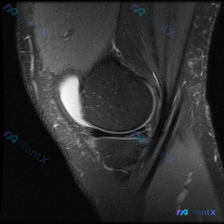

单幅膝关节MRI只看到髌上囊大量积液,半月板真的没异常?

本次是膝关节MRI T2序列矢状位单幅影像读片,初始问题是「这张图片里有什么可观察到的异常?」,初始提示提到可能存在半月板异常。

- 半月板:本次只显示了半月板前角和体部,影像范围内半月板内没有看到延伸到关节面的高信号撕裂表现

- 髌周结构:髌下脂肪垫、股四头肌腱、髌腱都没有明显异常;唯一明确的异常是髌上囊内看到大量T2高信号液体积聚,也就是明显的关节积液

一开始提示说可能有半月板异常,但我们读片不能被预设信息带偏。客观来看,本幅影像里唯一明确可观察到的异常就是髌上囊大量积液,半月板、主要韧带这些结构都没有看到明确损伤,所以我们得从「孤立性髌上囊积液」这个客观发现出发分析,不能硬找半月板异常。

- 隐匿性微小关节内损伤:比如单幅影像没拍到的微小软骨损伤、盘状半月板不稳定,或者非常轻微的韧带/半月板部分损伤,这些也可能刺激滑膜产生积液。但要强调:目前这幅影像里确实没看到明确的半月板撕裂